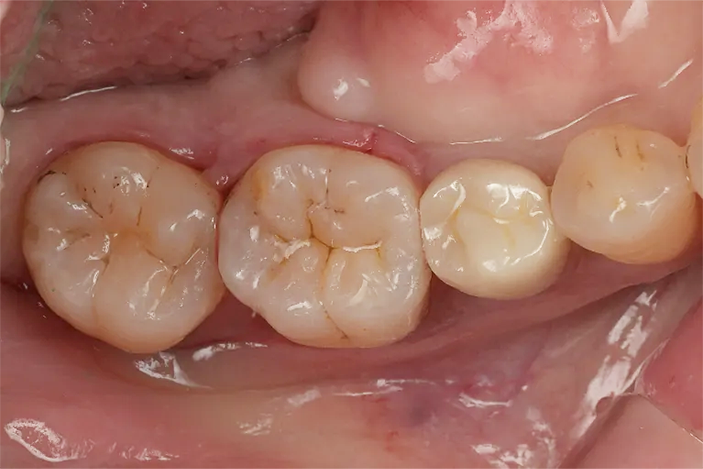

Case2

術前

ラバーダム防湿

術後

| 治療名 | ダイレクトボンディング |

|---|---|

| 治療説明 | 虫歯が発生したため、ダイレクトボンディングを行いました。ラバーダムを装着し、う蝕を除去してレジンを充填し、見た目と機能を回復しました。 |

| 治療回数・期間 | 1回 |

| 副作用とリスク | 知覚過敏症状が生じる恐れがあります。レジンが破折歯修復が必要となることがあります。 |

| 料金(税込) | 55,000円(自費) |